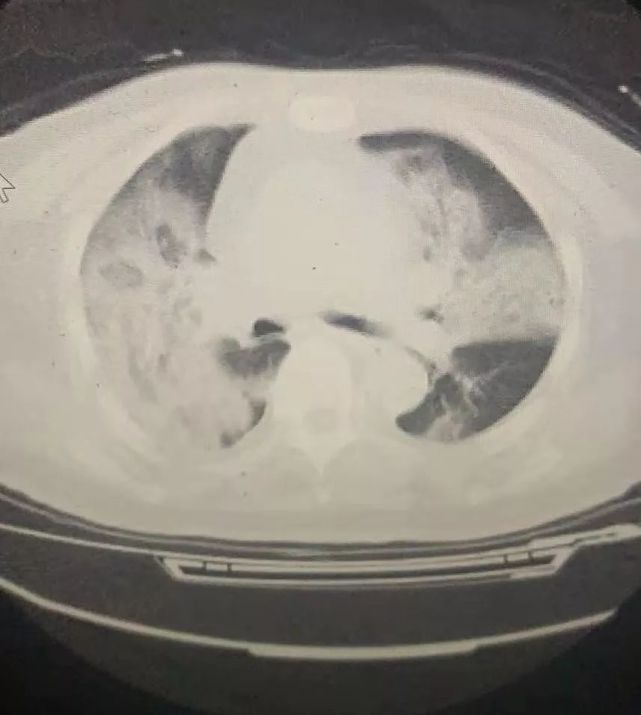

一名疑似患者的肺部CT图 , 肺部基本全“白”了 后来我才了解到 , 1月22日晚上 , 有三分之二的病人都曾在别的医院看过 。 但很多医院已经不收发热病人 , 引导患者到我们这些定点医院就诊 。 也有定点医院1月22日晚接到上级提前开始接诊的要求 , 但被院领导以未准备充分为由拒绝了 。 很多医生也没准备好 , 没有经历过传染病的救治 , 没有经验 。 比如武汉一家很好的医院的一个外科医生 , 接触了这样的病人也没有当回事 , 竟然去了医院的内科、急诊 , 发病也没有及时告知同事 , 其他人都跟着他一起感染 。 连当医生的都没有警觉 , 整个局面完全是被动挨打 。 3 1月21日接到我们医院要转为发热病人定点医院时 , 一名医生说孩子还很小 , 自己很害怕 , 想要辞职 。 我很理解她 , 我也很怕 。 但我为她职业发展的考虑 , 还是劝她坚守 。 我说 , 我可以批准你辞职 , 但这会给你留下“污点” , 未来去任何单位 , 你都会被当成是“逃兵” 。 她没有辞职 , 还作为一线医生经历了1月22日晚上医院最混乱的场景 。 没想到次日清晨回家后 , 她就开始出现被感染的症状 。 返回医院接受检查后 , 她被认为是疑似患者 , 但因为没有试剂盒而尚未确诊 。 我让她赶紧回家休息 , 她却说 , “主任 , 我找个地方查一下吧 。 如果不是 , 我还想回来和大家一起战斗 。 ”我当时想 , 如果她痊愈了 , 这就只是一个遗憾;她才20多岁 , 万一出了事 , 我作为她的主任怎么活下去?我怎么赔这个家庭一个女儿、一个妈妈 。 这件事情让我很难过 , 我怕影响军心 , 一个人躲到外面哭了很久 。 我们有一位医生 , 孩子才7个半月 , 本来是可以回家过年的 。 但疫情爆发后 , 她强行把孩子的母乳断掉 。 另一个医生 , 让亲戚带着两个孩子回老家 , 她丈夫也是大夫 , 早就上了一线 。 一天晚上人员特别缺乏 , 她在一线顶了一夜 。 考虑到她的健康 , 我没有在后一天排她的班 。 结果她看到排班表后 , 来找我 , 说自己随时待命 , 该怎么上班就怎么上班 。 还有一名70多岁已经退休的老主任给我发来短信 , 说如果需要 , 自己随时回来顶班 。 我们做这些不求什么表扬 , 只求病人平平安安 , 只求自己平平安安 。 这不是什么漂亮话 , 是医生的基本道德 。 说句实话 , 在这里的人没有不怕的 , 不怕都是假的 。 我们明知道这里面是个大污染区 , 但都顶在一线 。 大家选择一起住在宾馆、待在医院 , 就是想能互相壮胆 , 互相安抚 。 最近半个月 , 我每天只能睡2、3个小时 , 因为要协调安排的事情太多了 。 手机里一有医生护士的消息我就马上回 , 我就是想让他们知道 , 即便我暂时不在医院 , 我也和他们在一起 。 很多人怕感染家人 , 也为了随时待命 , 就住在医院安排的酒店里 。 但医院的食堂只给值班人员提供伙食 , 在宾馆休息的医护人员就吃些泡面和零食 。 我家在医院附近 , 下了班有空时 , 就会做饭给他们送去 。 因为自己是高危人群 , 我让儿子出去住 , 但我的亲戚不愿意让儿子去他们家 , 因为怕被传染 。 可我的儿子也不会做饭 , 每天就下点面条 , 或是泡面吃 。 除夕夜 , 我给我的亲戚打电话 , 让她炒一个菜 , 放到儿子住处的楼下就行 , 儿子自己下去拿 , 起码让他大过年的能吃一顿好饭 。 我在家里烧菜给我的医生吃 , 可是没有人给我的儿子烧菜吃 , 你说我的心不痛吗? 4 除夕夜 , 网上流传好几段医生在办公室崩溃大哭的视频 。 这是真的 , 有一段视频中的医生就是我们医院的 。 另一个视频里 , 情绪激动打电话的男医生也是我们医院的 。 事实上 , 由于过度紧张疲惫 , 每个科室的医生们不知道都哭了多少次了 。 死亡让我流泪 。 我接手过一个病人 , 肺部已经完全纤维化了 , 我看着她的血氧从80降到70、60 , 一点点往下掉 。 她抓着你的手 , 说医生求求你救救我 。 你说当医生的看到这一幕谁能受得了 。 我们愿意拼命 , 但基本的保障要解决啊 。 脱下防护服后 , 每个人一身汗 , 可医院只有两个时段有热水 , 时间一旦错过 , 就没法洗澡 。 医院安排的宾馆 , 一个科室只给两间房 , 根本不够睡 , 只能一张床挤两个人 。